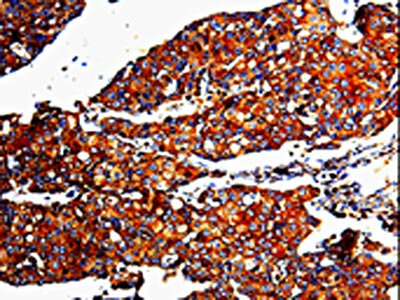

The image is immunohistochemistry of paraffin-embedded Human breast cancer tissue using CSB-PA014205(MMP3 Antibody) at dilution 1/10. (Original magnification: ×200)

The image is immunohistochemistry of paraffin-embedded Human cervical cancer tissue using CSB-PA014205(MMP3 Antibody) at dilution 1/10. (Original magnification: ×200)